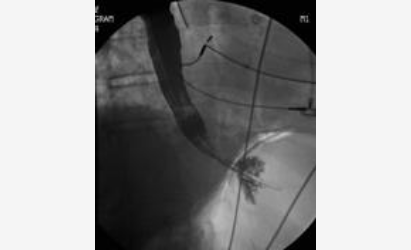

This patient’s chest radiographs reveal a pneumomediastinum, which in the clinical context of protracted vomiting raises reasonable concern for esophageal rupture (Boerhaave’s syndrome). Assessment for possible esophageal leak by fluoroscopic study would be the next appropriate step. When this study was performed (Figure 6), an esophageal leak was identified, and the patient was taken for emergent surgical repair. CT scanning can also be helpful to determine the extent of injury.

- Fluoroscopic esophageal study revealing dye extravasation.